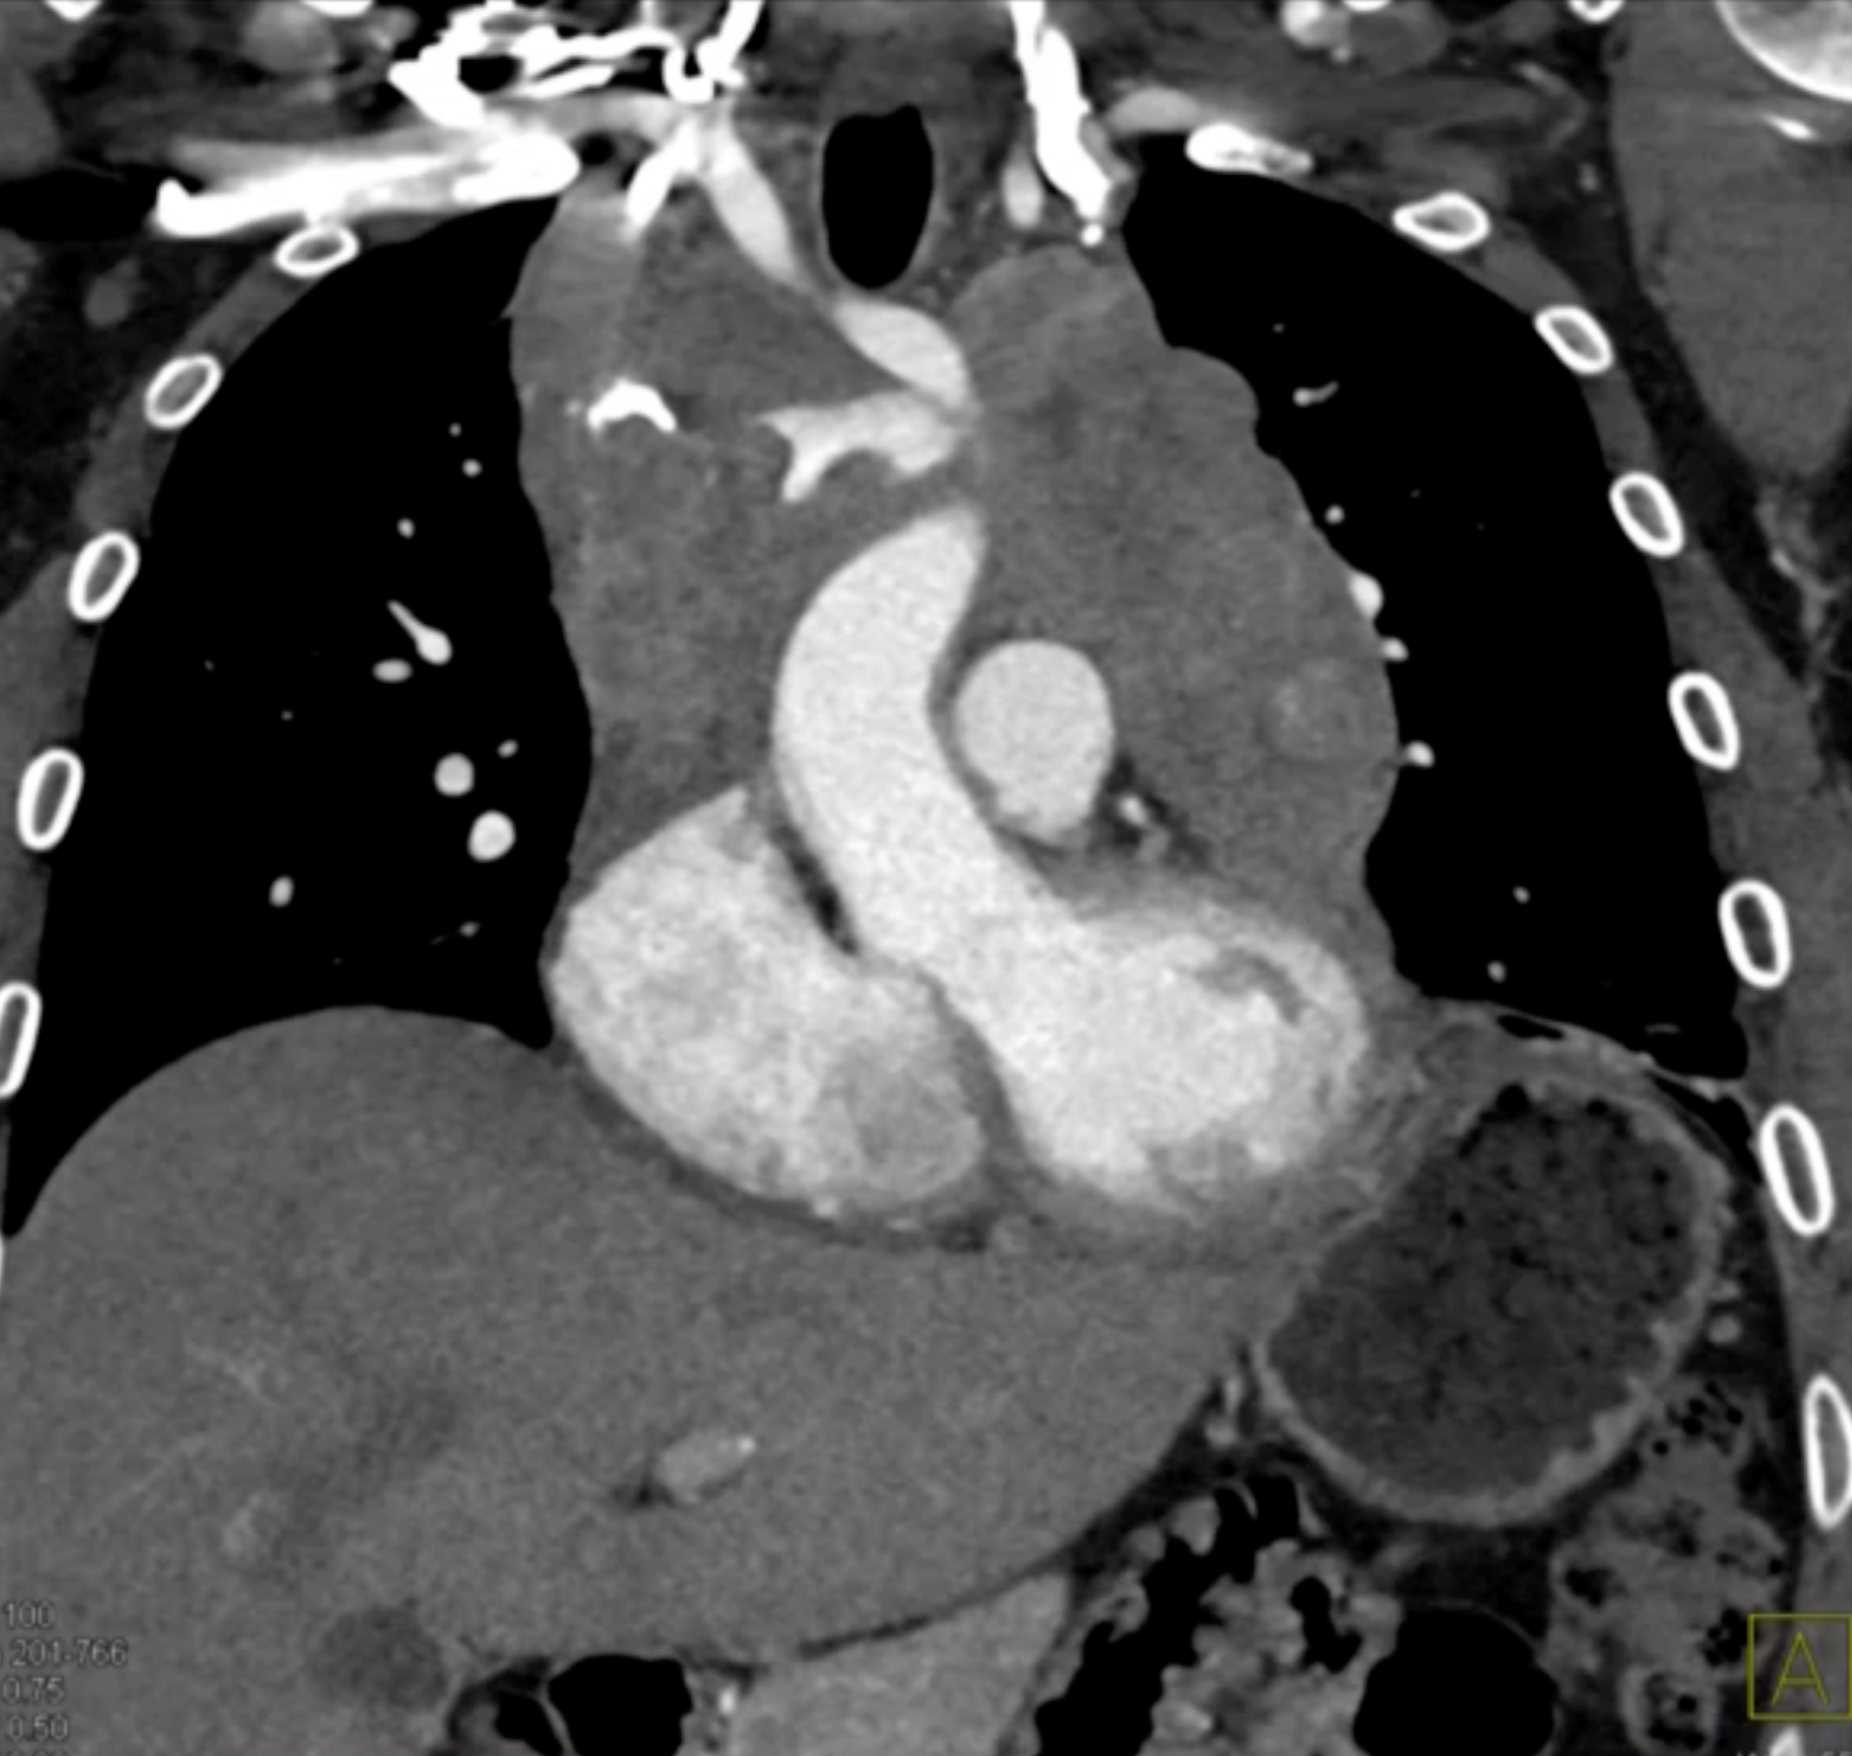

Thymic Carcinoma